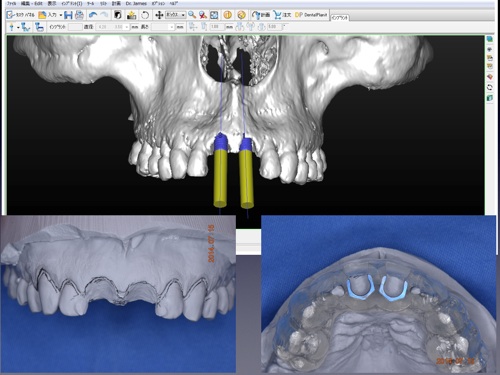

インプラント治療を安全に行うため、当院ではCT分析ソフト(SimPlant)を用い診断、シミュレーションを行っております。

以下の画像のように詳細な情報が得られることがお分かりいただけると思います。

安 全・安心・正確なインプラント治療

当クリニックでは安全・安心・正確なインプラント治療のためガイド手術を行っております。